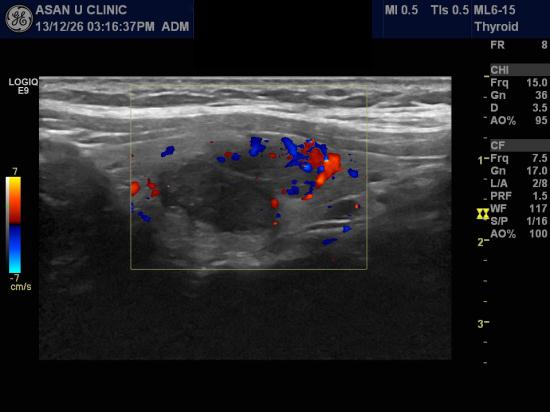

아산유외과 개원 후 15번째 갑상선암 진단.

건강검진상 갑상선 초음파에서 이상소견이 있어 의뢰된 50세 여성분입니다.

2.06cm의 혹을 세침검사하였고 갑상선의 유두암으로 진단되셨습니다.

증상이 없어도 검사를 해야하는가에 대한 질문을 많이 받습니다.

갑상선의 혹은 커지면서 증상이 시작되기에 작은 크기에 진단되는 경우는

대부분 건강검진시 우연히 발견됩니다.

우리나라의 건강검진의 발달과 함께 갑상선암 환자가 증가하는 이유가 그때문입니다.

당신의 갑상선은 안녕하신가요?